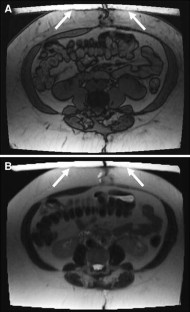

Fig. 2